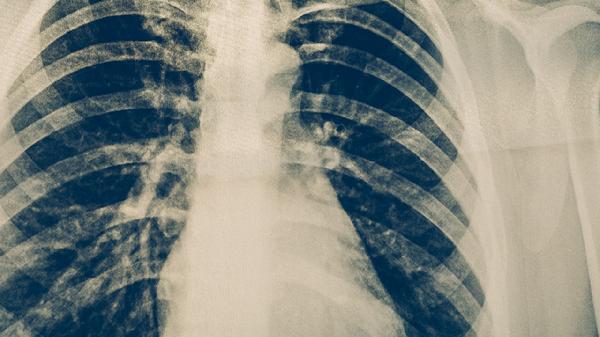

肺結(jié)核可通過接種卡介苗、保持通風(fēng)、佩戴口罩、增強(qiáng)免疫力、定期篩查等方式預(yù)防。肺結(jié)核是由結(jié)核分枝桿菌感染引起的慢性傳染病,主要通過飛沫傳播。

結(jié)核菌素試驗(yàn)或γ-干擾素釋放試驗(yàn)適合高風(fēng)險(xiǎn)人群篩查??人钥忍党^2周者需進(jìn)行痰涂片和胸部X線檢查。密切接觸者應(yīng)每半年復(fù)查一次,學(xué)生及醫(yī)務(wù)人員建議每年體檢。發(fā)現(xiàn)疑似癥狀應(yīng)立即到結(jié)核病定點(diǎn)醫(yī)療機(jī)構(gòu)就診。

日常生活中應(yīng)注意與咳嗽患者保持1米以上距離,不隨地吐痰,咳嗽時(shí)用肘部遮擋口鼻。保證每日攝入300克新鮮蔬菜和200克水果,適量食用大蒜、洋蔥等具有抗菌作用的食物。出現(xiàn)長(zhǎng)期低熱、盜汗、消瘦等結(jié)核中毒癥狀時(shí),須及時(shí)進(jìn)行結(jié)核菌檢測(cè)和影像學(xué)檢查。確診患者應(yīng)嚴(yán)格完成6-8個(gè)月的規(guī)范治療,避免產(chǎn)生耐藥性。